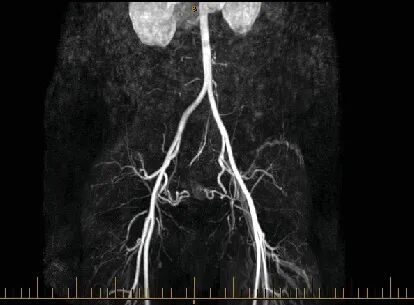

为了看清这团血管的真面目和它的势力范围,医生安排她做了CT血管造影。

这个检查就像给子宫的血管系统拍了一张高清三维地图,放射科的医生看了之后,确认了这是子宫动静脉畸形。

手术非常成功,几个月后复查血管核磁共振,显示那个血管团已经显著缩小,血流信号几乎消失。

当然,增强CT或核磁共振血管成像能清晰显示畸形血管团的位置、大小、范围以及它和周围血管的关系,对于制定治疗方案至关重要。